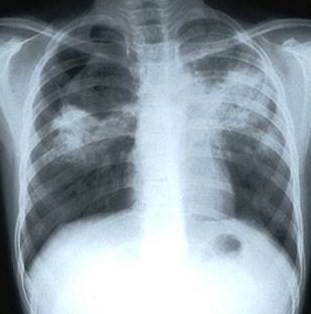

Tubercolosi in Emilia Romagna.

L’AUSL di Reggio Emilia ha infatti individuato un caso di tubercolosi polmonare in un soggetto adulto, venuto a contatto con il personale e gli alunni del’ “Amedeo d’Aosta”, una scuola media

statale. I sintomi della malattia si sono manifestati durante l’estate ma, considerato il lungo periodo d’incubazione, non è da escludere il rischio per chi è venuto a contatto

con il soggetto negli ultimi mesi dello scorso anno scolastico.